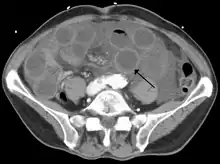

Computed tomography (CT) showing dilated loops of small bowel with thickened walls (black arrow), findings characteristic of ischemic bowel due to thrombosis of the superior mesenteric vein.

Early findings on CT scan include:

• Intestinal mesenteric edema[29]

• Bowel dilatation[29]

• Bowel wall thickening[29]

• Intestinal mesenteric stranding[32]